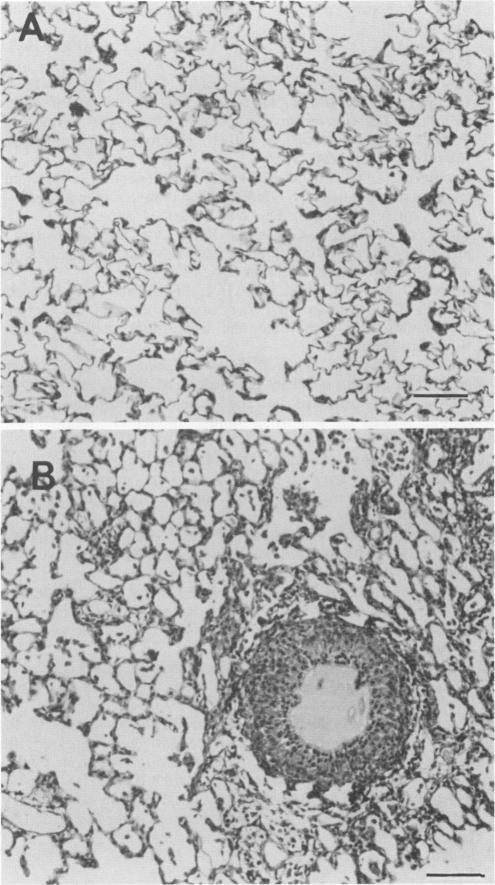

Outer membrane protein F (porin) was purified by extraction from polyacrylamide gels of cell envelope proteins of the Pseudomonas aeruginosa PAO1 strain. Rats were immunized intramuscularly with 25 micrograms of protein F on days 1 and 14 and then challenged on day 28 via intratracheal inoculation of bacterium-containing agar beads. On day 35 the lungs were either fixed for histological examination or submitted for quantitation of the bacteria present. protein F immunization afforded significant protection against challenge with six of six heterologous lipopolysaccharide immunotype strains of P. aeruginosa. By an enzyme-linked immunosorbent assay, the protein F-immunized rats had both immunoglobulin G and M antibody responses to cell envelopes of all six of the heterologous immunotype strains. Protein F immunization greatly enhanced the ability of the rats to clear the inoculated P. aeruginosa from the lungs and significantly reduced the incidence and severity of pulmonary lesions as compared with those in bovine serum albumin-immunized control rats. These data show the efficacy of outer membrane protein F as a protective vaccine in a rat model of chronic pulmonary infection.

外膜蛋白F(孔蛋白)通过从铜绿假单胞菌PAO1菌株的细胞包膜蛋白聚丙烯酰胺凝胶中提取而纯化。在第1天和第14天,用25微克蛋白F对大鼠进行肌肉注射免疫,然后在第28天通过气管内接种含细菌的琼脂珠进行攻毒。在第35天,将肺固定用于组织学检查或送去定量其中存在的细菌。蛋白F免疫为抵御六种异源脂多糖免疫型铜绿假单胞菌菌株的攻毒提供了显著保护。通过酶联免疫吸附测定法,经蛋白F免疫的大鼠对所有六种异源免疫型菌株的细胞包膜都有免疫球蛋白G和M抗体反应。与牛血清白蛋白免疫的对照大鼠相比,蛋白F免疫大大增强了大鼠从肺部清除接种的铜绿假单胞菌的能力,并显著降低了肺部病变的发生率和严重程度。这些数据表明外膜蛋白F作为慢性肺部感染大鼠模型中的一种保护性疫苗具有有效性。